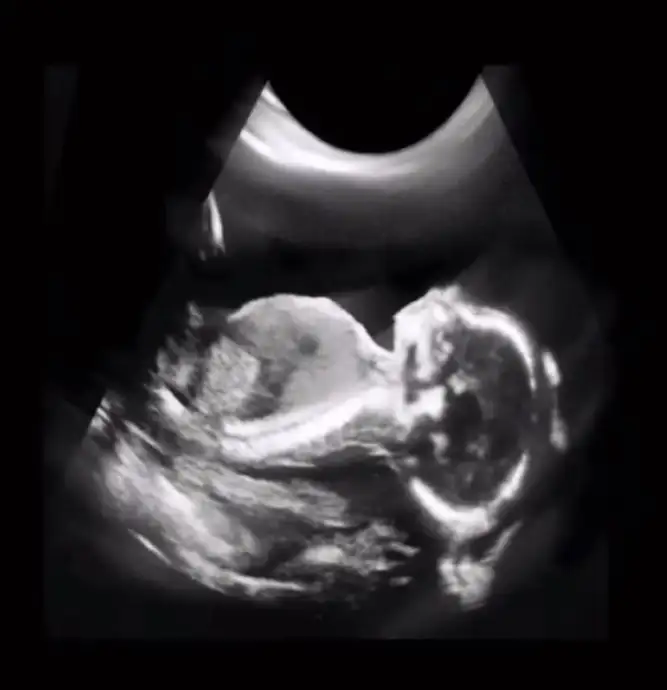

Sizce belli mi ben anlayamadım bir türlü??